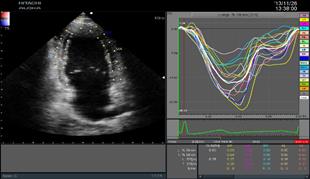

二維心肌組織追蹤2DTT

(2D Tissue Tracking)

ARIETTA 70-02模式匹配技術(shù)準(zhǔn)確識別并跟蹤感興趣的點,智能化分析心肌節(jié)段運動,準(zhǔn)確評估心肌局部運動功能及各節(jié)段運動的協(xié)調(diào)性,構(gòu)建左室“牛眼圖”,直觀顯示心室各段功能狀態(tài)。